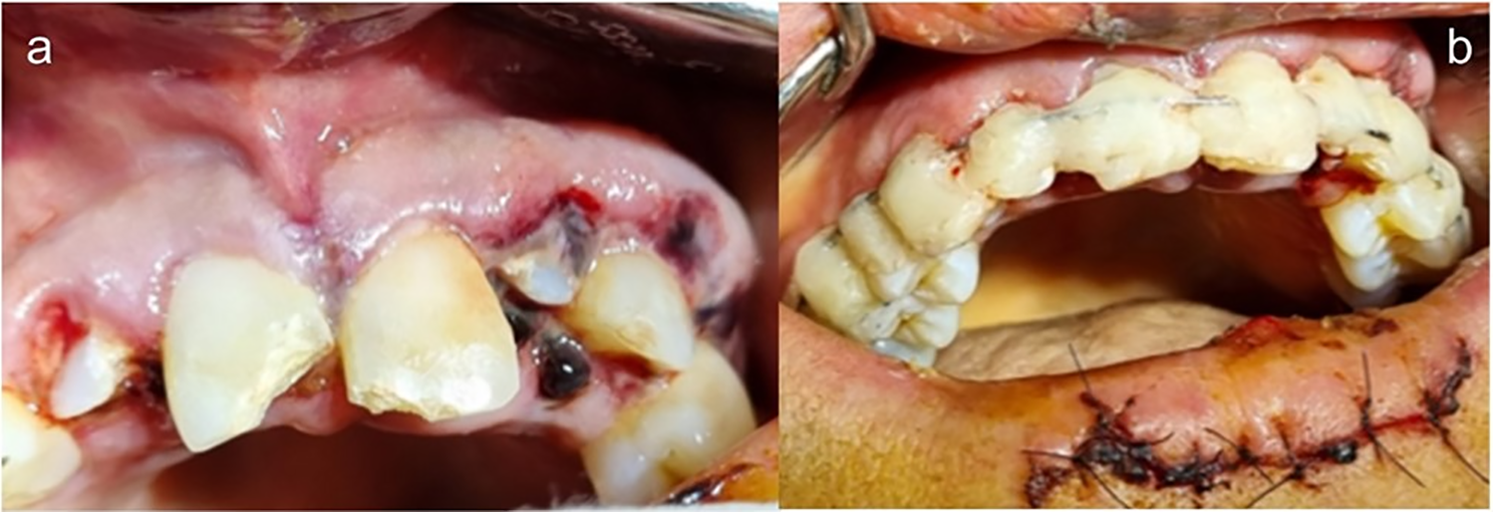

48 hours after TDI, all luxated and/or intruded teeth (LI on the lateral incisors and right canine and LL on the central incisors Fig. 4a) were properly repositioned with digital traction, except for the left canine, which was severely impacted and therefore gently and carefully removed using the appropriate extraction forceps. Venous flow was immediately reestablished, and the skin of the nose and suborbital region turned bluish. After the teeth were correctly repositioned, the multiple fractures were reduced manually with digital pressure on the fractured ends, relocating the fragments to coincide with the pre-existing three-dimensional positions of the tooth roots. The enamel of the dental elements on the buccal surface (middle third) of the teeth from the right first molar to the left first molar was etched with 37% orthophosphoric acid. After washing with plenty of water and drying, the surfaces were impregnated with 3M® Single Bond adhesive for subsequent photocuring with a halogen light. A 19 × 25 stainless steel orthodontic archwire was selected and adapted to splint the 12 dental elements of the maxilla. 3M® Z350 nanoparticle paste was used to firmly fix the archwire to the dental surfaces, thus creating a rigid splint to simultaneously stabilize the traumatized teeth and reduce bone fractures of the maxilla (Fig. 4b). A nutritional plan was established that included a daily intake of 60 g concentrated whey protein and a soft diet for 45 days. In addition, it was supplemented with transresveratrol 100 mg/day + Vitamin E 20 mg/day (Framintrol ®) to promote bone healing because its antioxidant effects and potent anti-inflammatory and analgesic properties, as it exerts regulatory effects on various cellular processes, such as apoptosis, cell cycle progression, angiogenesis and immune responses [14], [15].

Fig. 4. Therapeutic intervention at 48hs: a) preoperative, b) splinting.